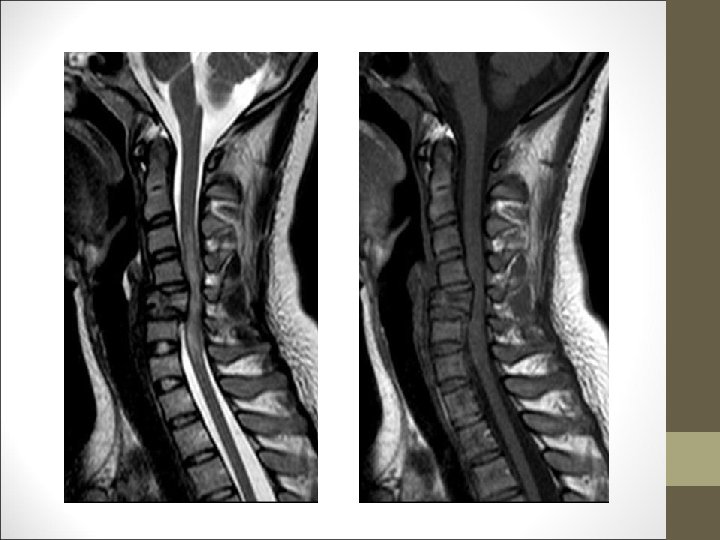

TC Desplazamientos de fragmentos óseos ¿Algo mas? FACULTAD DE MEDICINA DEPARTAMENTO DE CIRUGÍA NEUROCIRUGÍA RM Desplazamientos discales y lesiones ligamentosa